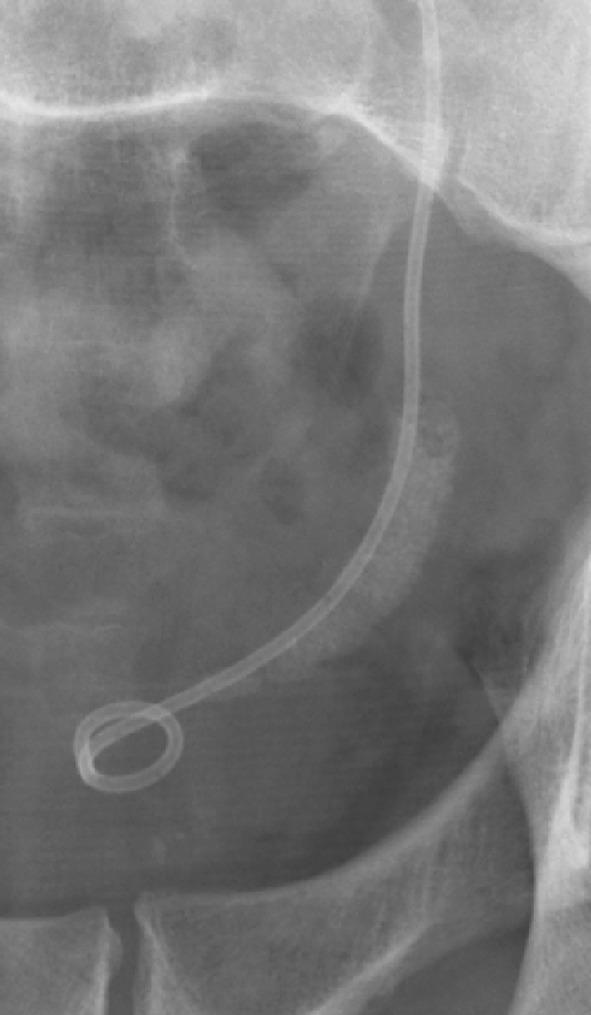

It is well recognized that the popularity of extracorporeal shock wave lithotripsy (SWL), despite its non-invasive character, has decreased during recent years. This is partly explained by the technological achievements in endoscopy and urologists' enthusiasm for such procedures. Another explanation is that many urologists have been insufficiently successful with SWL. The latter effect might to some extent be a result of the performance of the lithotripter used, but in too many cases, it is evident that the principles of how shock wave lithotripsy should be carried out are poorly applied. The purpose of this article is to emphasize some important aspects on how SWL best should be used. Based on decades of experience, it stands to reason that success with SWL does not come automatically and attention has to be paid to all details of this technique.